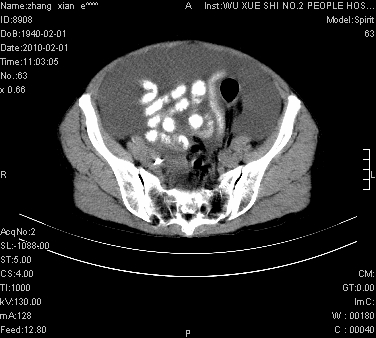

标题: CT24434:70岁 女 腹胀,腹水原因待查 [打印本页]

标题: CT24434:70岁 女 腹胀,腹水原因待查

大量腹水,脾脏囊性占位,子宫颈占位,右侧腹股沟淋巴结肿大,建议+c,先查妇科。

腹盆腔大量积液,子宫增大,子宫颈增大外形不规则,内见低密度影,膀胱后壁显示不清,右腹股沟肿大淋巴结,脾脏囊性占位,子宫颈占位,子宫颈癌?建议增强。

子宫、宫颈占位?转移性腹水?肝性腹水?脾脏囊性占位,囊肿?血管瘤?淋巴瘤?